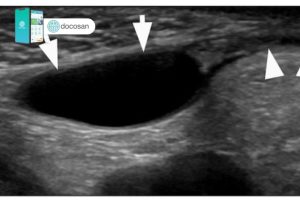

Bệnh lý giãn tĩnh mạch thừng tinh 2 bên xảy ra khi có sự giãn rộng các tĩnh mạch nằm ở trong bìu. Bệnh có thể ảnh hưởng đến sự sản xuất tinh trùng của tinh hoàn, suy giảm chất lượng tinh trùng. Hãy cùng Docosan tìm hiểu bệnh giãn tĩnh mạch tinh 2 bên nhé! […]